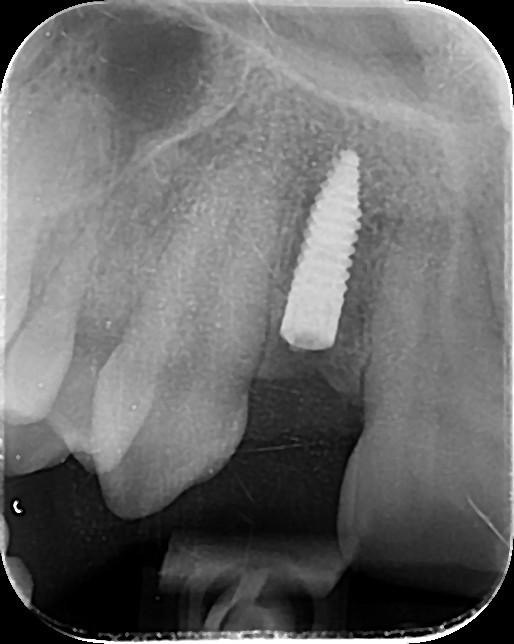

3. What option can be selected regarding the implant seen in this X ray?